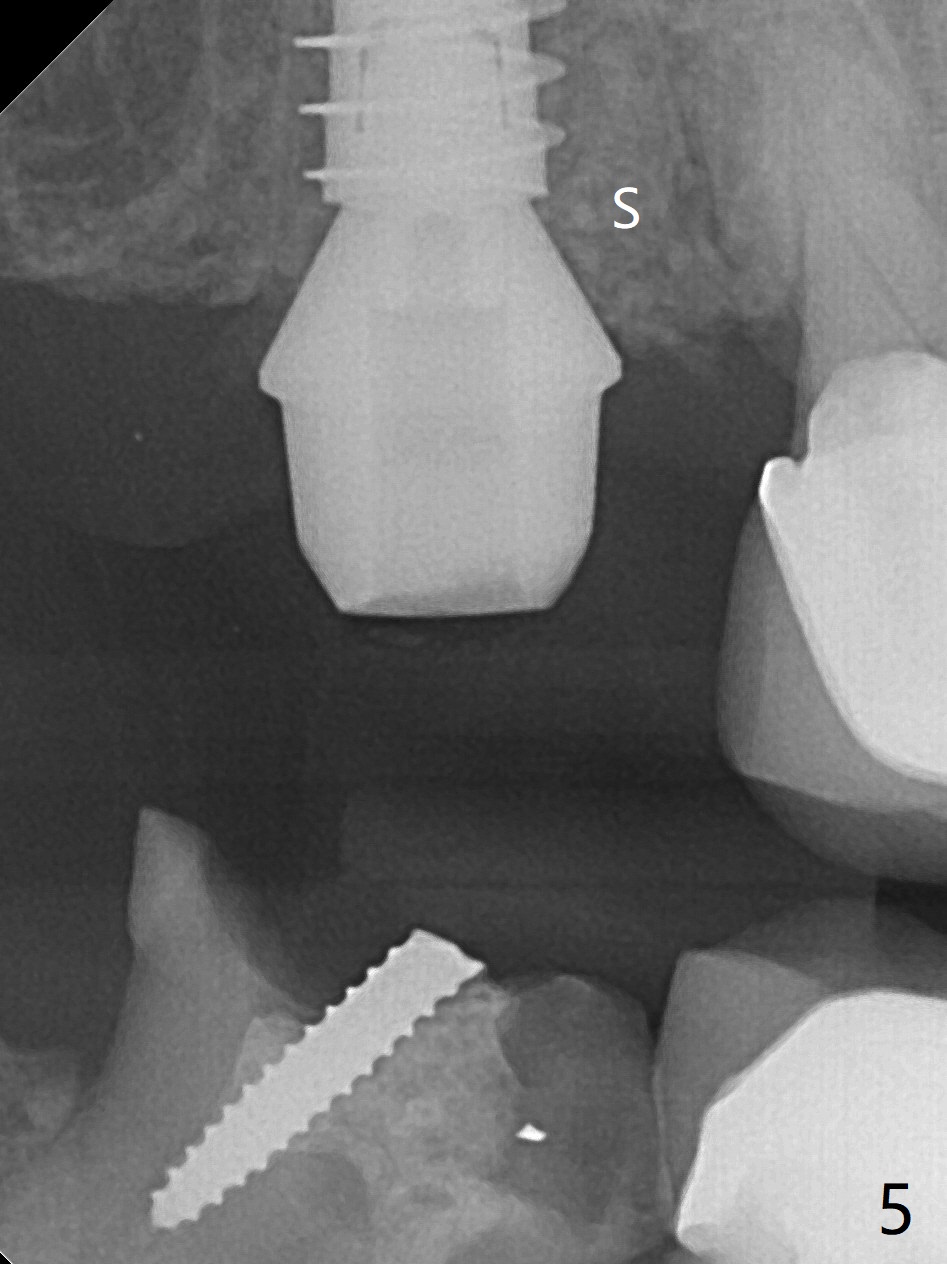

When the tooth #2 is extracted, there is sinus perforation in the palatal apex, consistent with preop CT (Fig.1: P). There is no bone shaving associated with drill sequence in the buccal socket (until 3.5x8.5 mm). With sticky bone and 4.5x10 mm IS dummy implant, sinus lift does not happen. Sinus floor perforation is felt when a 2.2x10 mm drill is used slowly. But air leaks from the palatal socket. With bone graft, a 4x10 mm dummy implant lifts the sinus (Fig.2). After further graft and 4.5x10 mm dummy implant, a 5x11 mm final implant is placed with 15 Ncm with sinus lift (Fig.3,4 *). Following abutment insertion, sticky bone is packed around the implant and abutment (Fig.5,6 S). Prior to final implant placement, a small piece of PRF and collagen and Osteogen Plugs are placed in the palatal socket for repair. Before discharge, there is mild nasal hemorrhage.